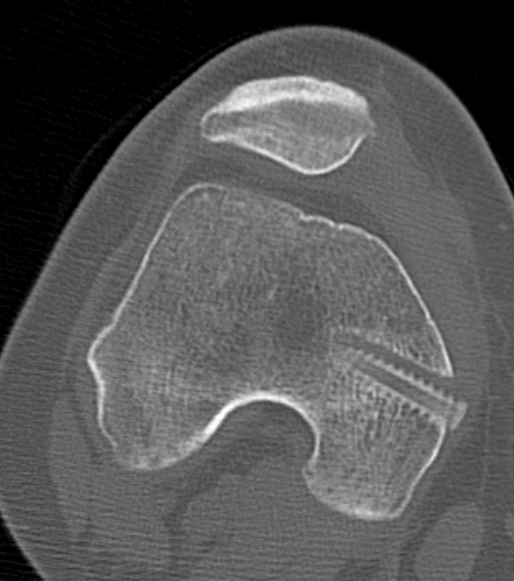

2. Perform TTT (if TTTG > 20)

- incision over TTT

- medialise at least 1 cm

- ensure some element of Fulkerson / anteriorise

- can distalise if patella alta

- secure with screws (2 x small fragment usually sufficient)

- reassess stability

3. MPFL reconstruction (with TTT, or if TTTG < 20)

- acts as checkrein to lateral displacement